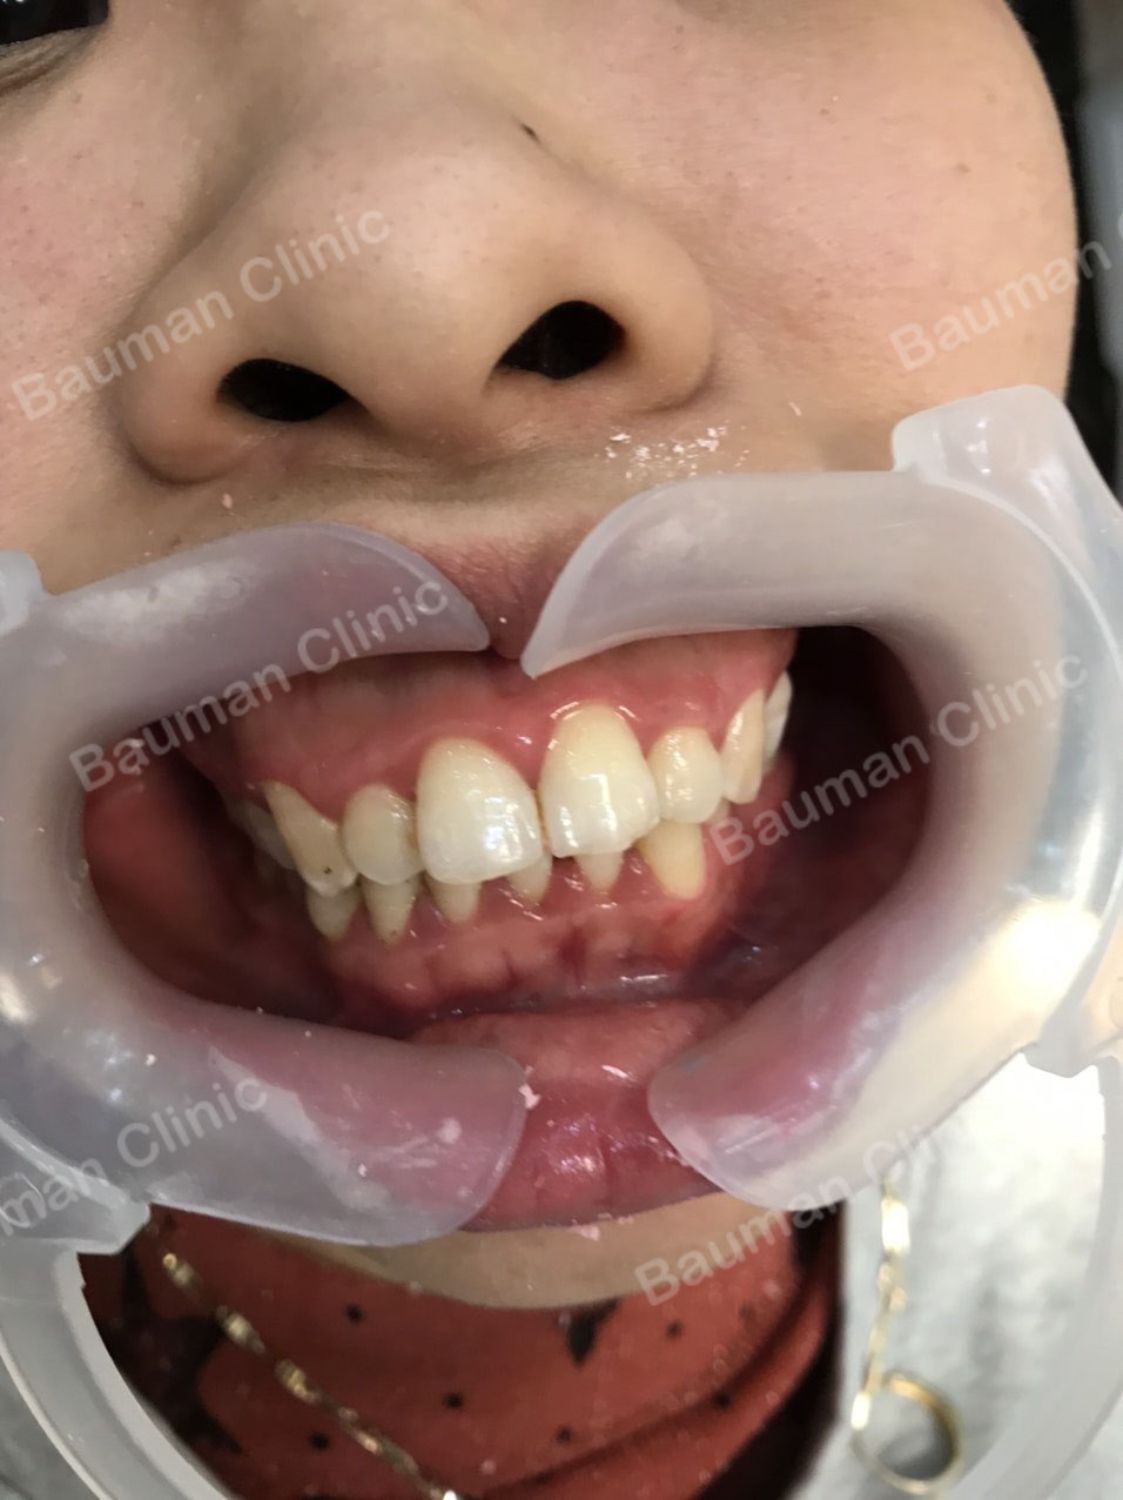

Ca niềng răng số 5094 - Nha khoa Bauman Clinic

Ca niềng răng số 5094: Tình trạng khô, khớp cắn sâu. Bạn lựa chọn niềng răng mắc cài sứ truyền thống.

Thời gian niềng răng dự kiến: 24 tháng. Cả nhà chờ đón kết quả nhé!